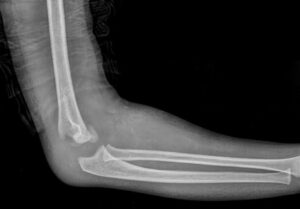

[toggle title=”Anterior Humeral Hat” state=”close”]

Lateral grafide humerus ön yüzeyine paralel ve bitişik çekilen çizgi kapitulumun 1/3 ortasından geçmelidir.

Bu hattın öne ya da arkaya yer değiştirmesi suprakondiler humerus kırığını destekler.

Aynı zamanda suprakondiler kırık hattıyla beraber posterior yağ yastıkçığı bulgusu da görülmekte

Bununla beraber kırık hattı ve posterior yağ yastıkçığı bulgusu da seçilmekte.

[box type=”info” align=”” class=”” width=””]Ancak yapılan çalışmalar <2.5 yaş çocuklarda kapitulumun küçük boyutu nedeniyle kırık olmayan normal grafilerde de anterior humeral hattın kapitulum önünden geçtiği görülmüş. Bu yüzden >2.5 yaş çocuklarda değerlendirilmesi daha doğru sonuçlar vermekte.[/box][/toggle]